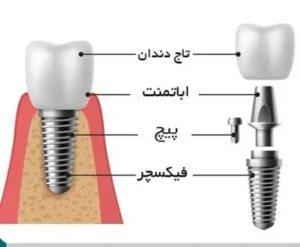

ایمپلنت دیجیتال :

ایمپلنت دندانی یکی از برجستهترین دستاوردهای دندانپزشکی مدرن است که جایگزینی دائمی و پایدار برای دندان از دست رفته محسوب میشود. در لابراتوار دندانسازی نگین ، ایمپلنتهای دیجیتال با استفاده از فناوری CAD/CAM و چاپ سهبعدی طراحی و ساخته میشوند. در این روش، ابتدا با کمک سیتی اسکن دندانی ، تصویر دقیقی از استخوان فک و دندانهای اطراف به دست میآید. سپس نرمافزارهای تخصصی محل دقیق قرارگیری ایمپلنت را تعیین کرده و راهنمای جراحی دیجیتال طراحی میشود. این فرآیند:

- خطای انسانی را به حداقل می رساند

- زمان جراحی را کاهش داده و بازیابی را تسریع میکند

- درد و تورم پس از عمل را به طور چشمگیری کاهش میدهد

- نتیجه نهایی را قاب لپیش بینی و مطمئن میسازد

ایمپلنت، لمینت و زیرکونیا :

لابراتوار نگین در حوزه رستوریشنهای پیشرفته نیز فعالیت گستردهای دارد. ساخت تاجهای روی ایمپلنت با دقت بالا، امکان جایگزینی کامل دندان از دست رفته را فراهم میآورد. ایمپلنتها با ایجاد پایهای محکم در استخوان فک، عملکرد دندان طبیعی را شبیهسازی کرده و از جذب استخوان جلوگیری میکنند. لمینتها یا روکشهای سرامیکی نازک، راهحلی زیباییمحور برای اصلاح دندانهای شکسته، تغییر شکل یافته یا دارای رنگ نامناسب هستند. این روکشها با حفظ حداکثر ساختار دندان طبیعی، لبخندی درخشان و یکدست ایجاد میکنند.